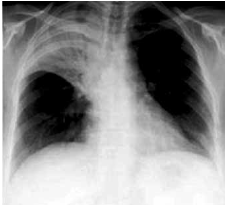

Homem, 37 anos de idade, etilista há 15 anos (2 litros de cerveja, 4 vezes por semana), foi levado ao pronto-socorro devido a febre, náusea, vômitos e desconforto respiratório há um dia. Exame físico: confuso, agitado e agressivo; PA: 160 x 105 mmHg, FC: 115 bpm, FR: 24 ipm, temperatura: 38,1 ºC e saturação de O2: 89%; abdome: fígado palpável a 6 cm do RCD. Radiografia de tórax mostrada a seguir.

Admitindo-se que a glicemia capilar (dextro) foi de 35 mg/dL, é correto prescrever